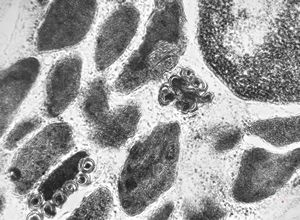

M,3y. | mast cell - granules with scroll-like formations - n. suralis, Krabbe globoid leukodystrophy

M,3y. | mast cell - granules with scroll-like formations - n. suralis, Krabbe globoid leukodystrophy

F,23y. | mast cell - granules with scroll-like formations - n. suralis, demyelinating neuropathy

F,31y. | mast cell - granules with scroll-like formations - n. suralis, demyelinating neuropathy

M,12y. | mast cell - granules with scroll-like formations - skin, urticaria pigmentosa